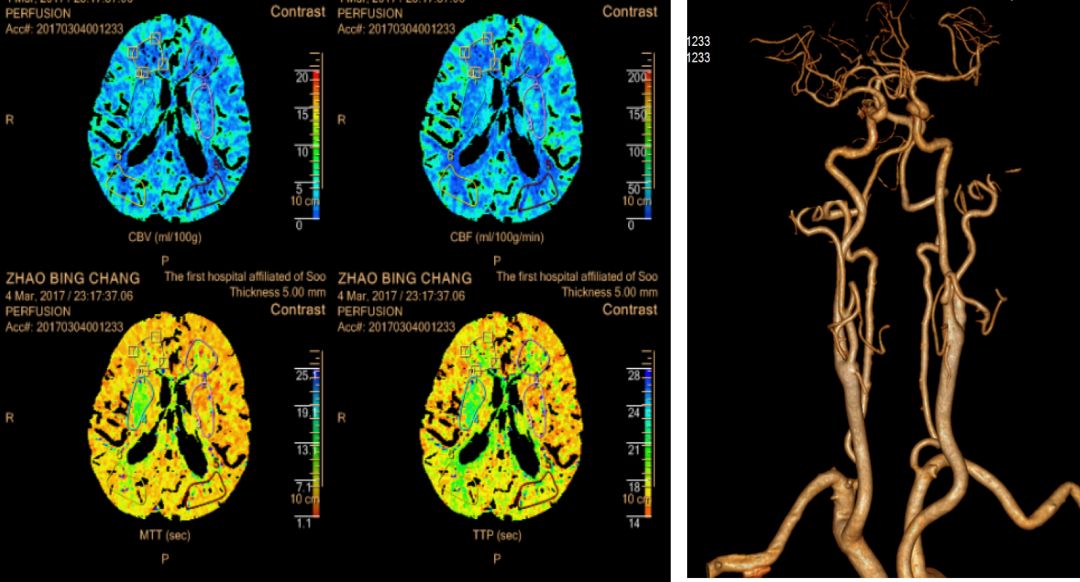

随即完善头颈部 CTA + CTP 检查:颅内外血管多发斑块形成伴管腔轻度狭窄,无血管内治疗指征。严密监测 24 小时,期间患者无新发症状出现,血压正常。

右侧颈外动脉起始段管壁局部软斑,伴管腔轻度狭窄,两侧颈内动脉 C4-7 段管壁多发钙化小斑块,伴管腔轻度狭窄;右侧半卵圆形中心及右侧侧脑室旁缺血灌注异常,存在缺血半暗带